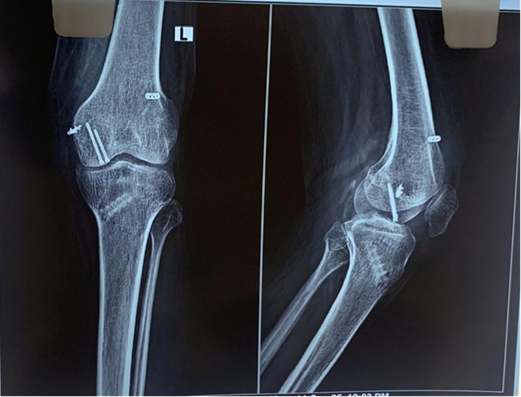

Two months post-operative X-rays were suggestive of healing of the Hoffa’s fracture (Fig. 8).

Figure 8: Two months post-operative X-rays.